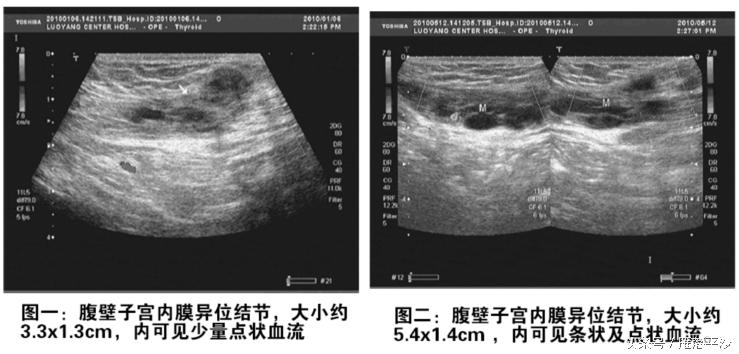

她婚后并未采取避孕措施,却一直不孕,后来去医院做了相关检查,查出子宫内有超过5公分的巧克力囊肿。她忍痛做了腹腔镜手术,剥离囊肿后的病理检测结果显示为良性子宫内膜异位症。医生说子宫内膜异位症患者很难自然怀孕,目前没有特效药,而怀孕是治疗它的最佳方法。